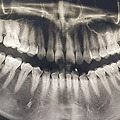

영케이 대단한 사랑니 작성자사라앙| 작성시간25.12.31| 조회수0| 댓글 46 본문 목록 댓글 리스트 작성자 The Evil Queen 작성시간25.12.31 나..양쪽 매복누운..근데 구강안면외과랑 치과에서 걍 살으래..ㅋㅋ30넘엇음 걍 살으라던디? 이미지 확대 더보기 신고 센터로 신고 카페 운영자 제보 작성자 어항 속 금붕어 작성시간25.12.31 나도 저래서 사랑니 전문병원 가서 뺐는데 ㅋㅋㅋ 더보기 신고 센터로 신고 카페 운영자 제보 작성자 번개맞고물고기됨 작성시간25.12.31 나도 저런꺼 잇어서 모른척하고 살다가 어느순간부터 뭔가 덜그럭 불편 느껴져서 결국 허겁지겁뺌 ㅠㅠㅠㅠㅠ 더보기 신고 센터로 신고 카페 운영자 제보 작성자 우가가가우가우 작성시간25.12.31 난 4개 다.. 누운 매복사랑닌데 부숴서 뺐지 머.. 더보기 신고 센터로 신고 카페 운영자 제보 작성자 DJ Tukutz 작성시간25.12.31 나도 누운 거 있는데 나는 안 나올 것 같다고 그냥 두라던데ㅠ 딱 안붙어서 그런가? 더보기 신고 센터로 신고 카페 운영자 제보 작성자 구구가 작성시간25.12.31 나도 네개 다 누워있는데 아무렇지도 않아서 냅두는중... 더보기 신고 센터로 신고 카페 운영자 제보 이전 목록이 없습니다. 1 2 현재페이지 3 다음 목록이 없습니다.